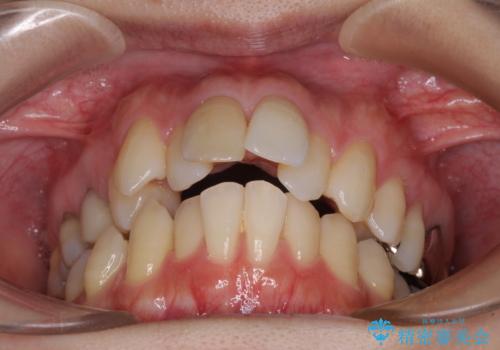

- 口を閉じたときに飛び出してしまう上顎前歯を気にして来院された患者様です。

上下の咬み合わせは上顎歯列全体が歯1本分前にずれている状態であり、さらに上顎歯列はV字型に尖っていたため、上下前歯は全く接触していない状態でした。

上顎左右第一小臼歯を抜去して、ワイヤー装置にて口元の突出感を改善するよう矯正治療を行うこととしました。